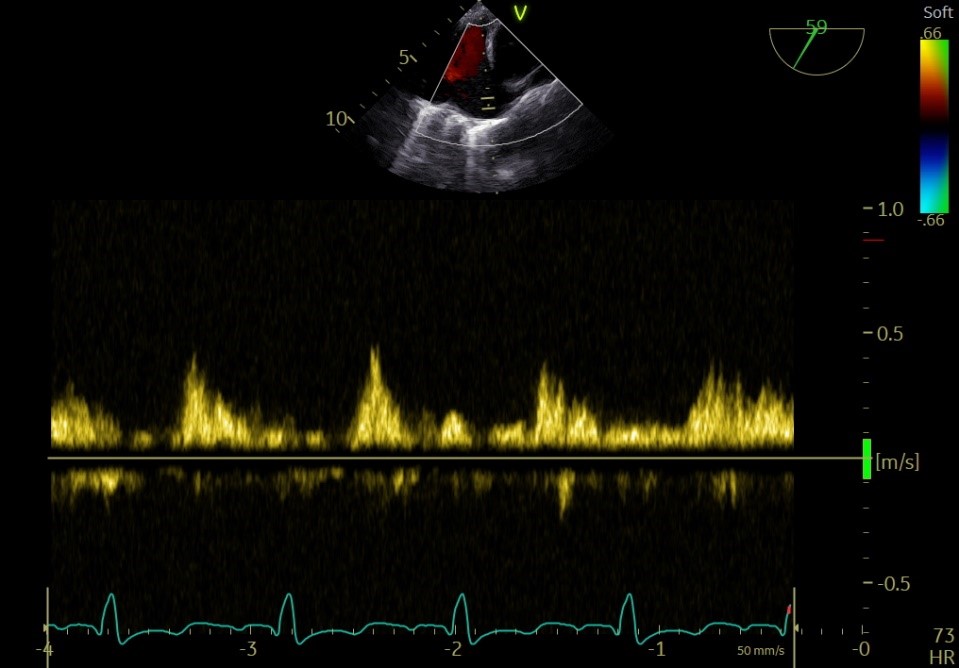

术前左房压

释放后

术后平均跨瓣压差

术后左房压